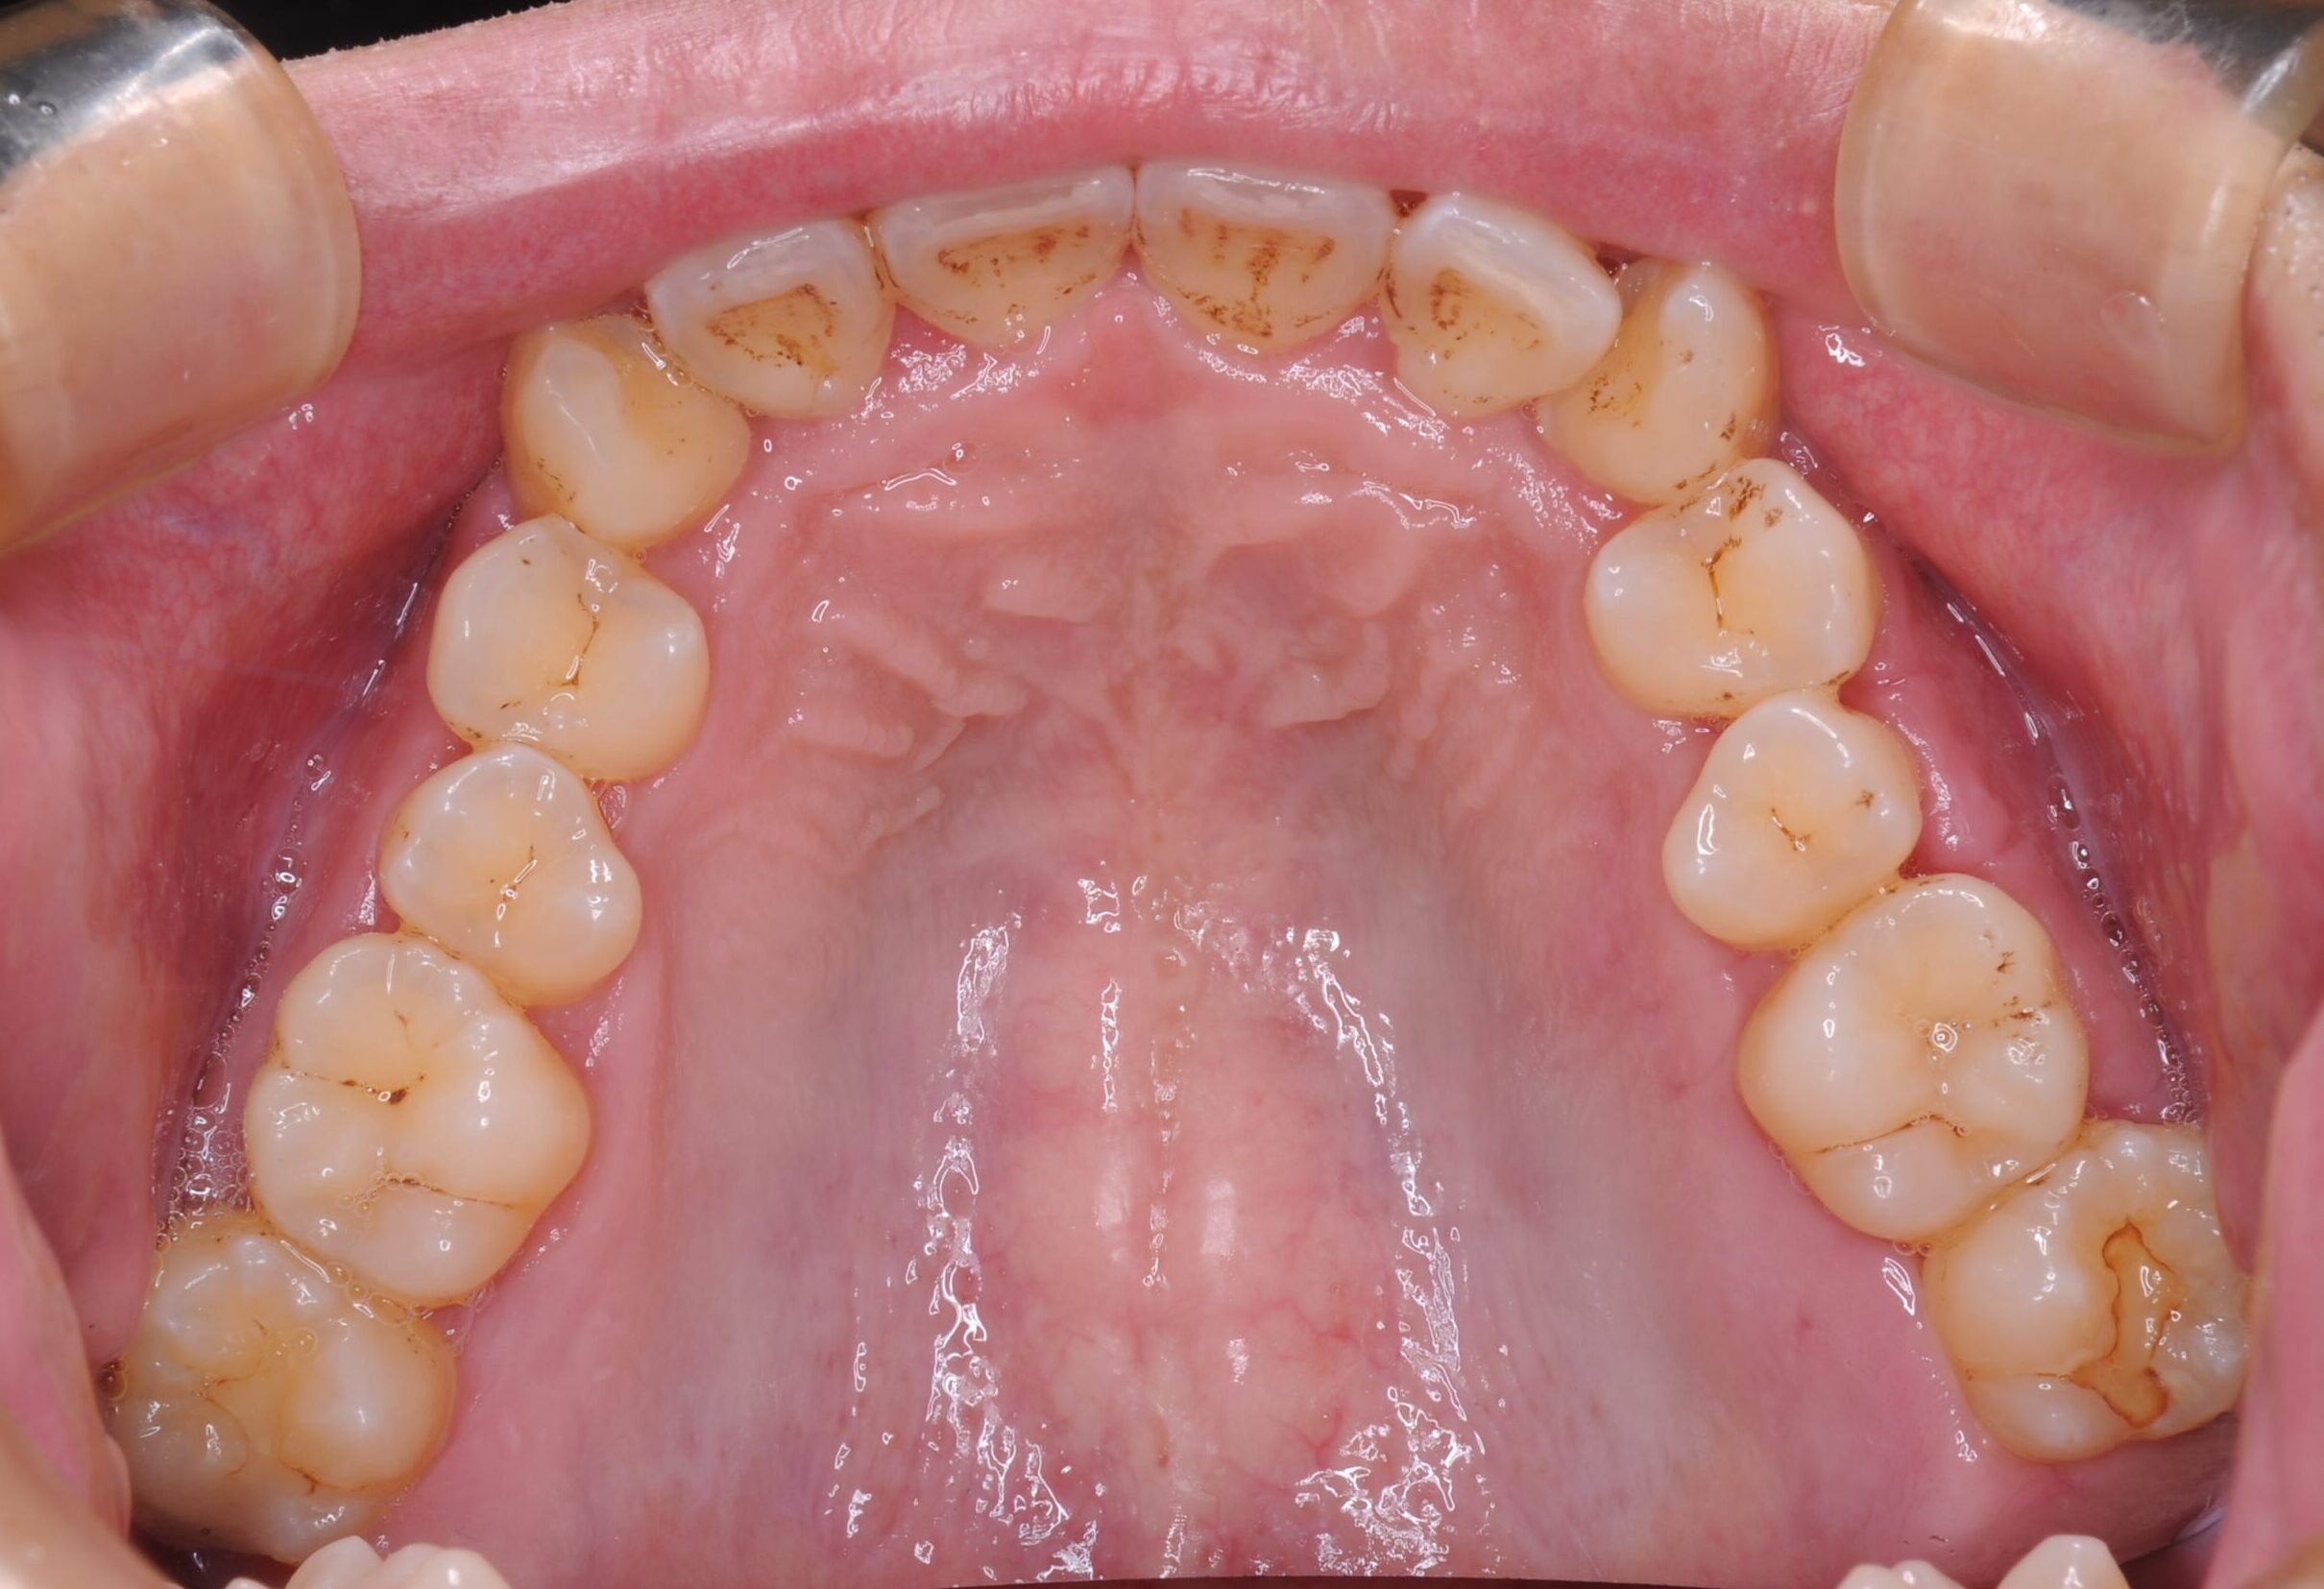

症例写真 before